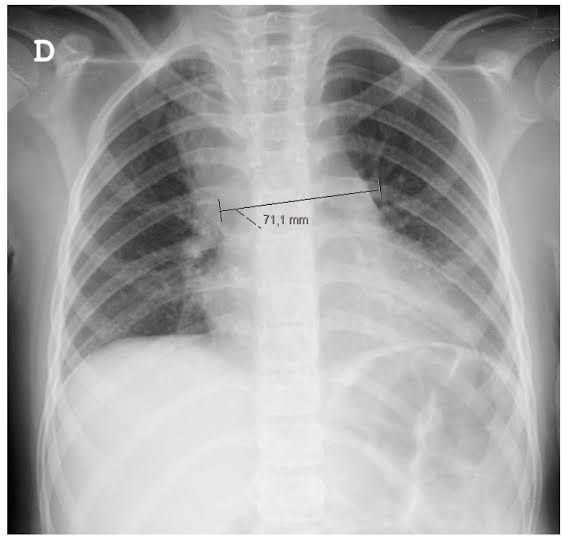

Mediastinitis is inflammation or infection in the part of your chest that contains your heart. It can be either acute (sudden) or chronic. Acute mediastinitis is usually due to complications from a median sternotomy or an esophageal tear. Symptoms include chest pain, fever and trouble breathing. Early treatment improves your chances of survival.